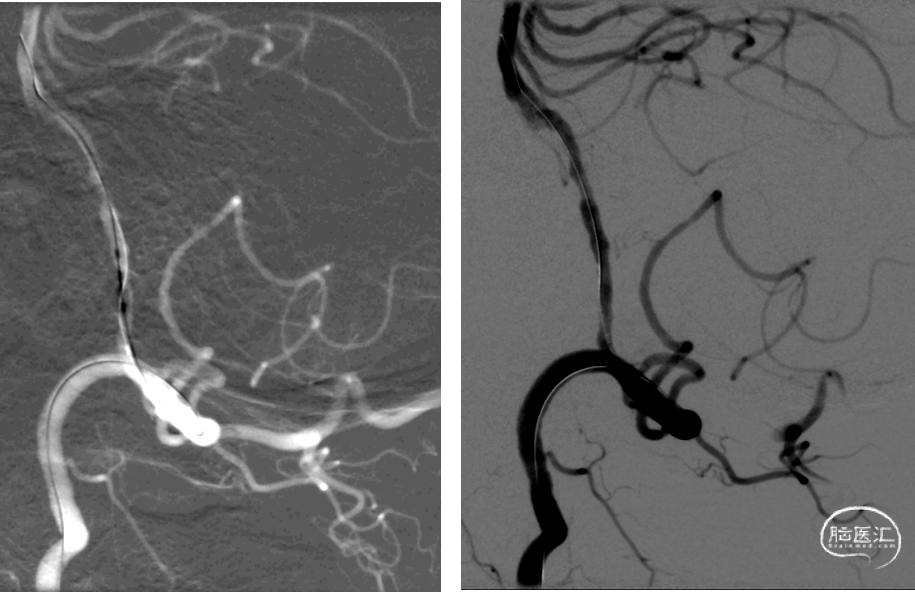

300cm微导丝携Gateway球囊到位,行球囊扩张及预扩张后造影。

术后结局

小结和体会

2、右侧椎动脉V4段血管狭窄附近未见有明确血管分支,因此手术选择了行右侧椎动脉V4段球囊扩张及支架置入术,因双侧椎动脉V4段狭窄以远椎动脉及基底动脉汇合处血管良好,因此右侧椎动脉V4段狭窄处支架置入术后病人右侧椎动脉及远端基底动脉血流明显改善外,同时也可见到左侧椎动脉V4段逆向显影至左侧小脑后下动脉。同时避免了左侧椎动脉支架置入术中对左侧小脑后下动脉的影响导致小脑后下动脉缺血事件发生的可能。

4、EZ支架通过性好,释放顺畅,径向支撑力强,支架贴壁良好。